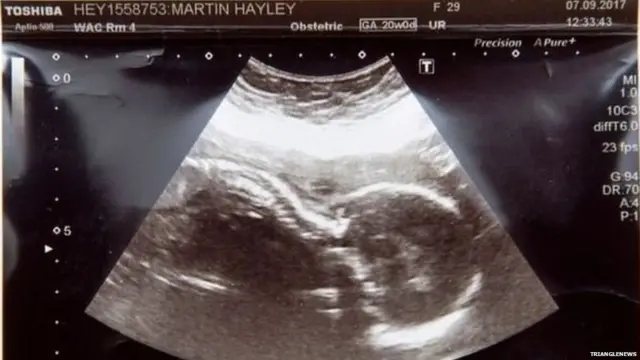

ਹਾਰਲੇ ਮਾਰਟਿਨ ਨੂੰ 20ਵੇਂ ਹਫ਼ਤੇ ਦੀ ਸਕੈਨਿੰਗ ਦੌਰਾਨ ਇਹ ਪਤਾ ਲੱਗਿਆ ਕਿ ਉਸ ਦੀ ਕੁੱਖ ਵਿੱਚ ਪਲ ਰਹੀ ਬੱਚੀ ਨੂੰ ਇੱਕ ਦੁਰਲੱਭ ਜਮਾਂਦਰੂ ਰੋਗ ਹੈ ਜਿਸ ਕਰਕੇ ਉਹ ਜਾਂ ਤਾਂ ਜਣੇਪੇ ਦੌਰਾਨ ਜਾਂ ਇਸਦੇ ਕੁੱਝ ਪਲਾਂ ਵਿੱਚ ਹੀ ਮਰ ਜਾਵੇਗੀ।

ਤਿੰਨ ਬੱਚਿਆਂ ਦੇ ਮਾਪਿਆਂ ਮਾਰਟਿਨ ਤੇ ਸਕੌਟ ਨੂੰ ਸਕੈਨ ਦੌਰਾਨ ਪਤਾ ਲੱਗਿਆ ਕਿ ਉਨ੍ਹਾਂ ਦੀ ਬੱਚੀ ਦੇ ਇੱਕ ਜਾਂ ਦੋਵੇਂ ਗੁਰਦੇ ਨਹੀਂ ਹਨ ਅਤੇ ਫ਼ੇਫੜਿਆਂ ਵਿੱਚ ਵੀ ਨੁਕਸ ਹੈ।